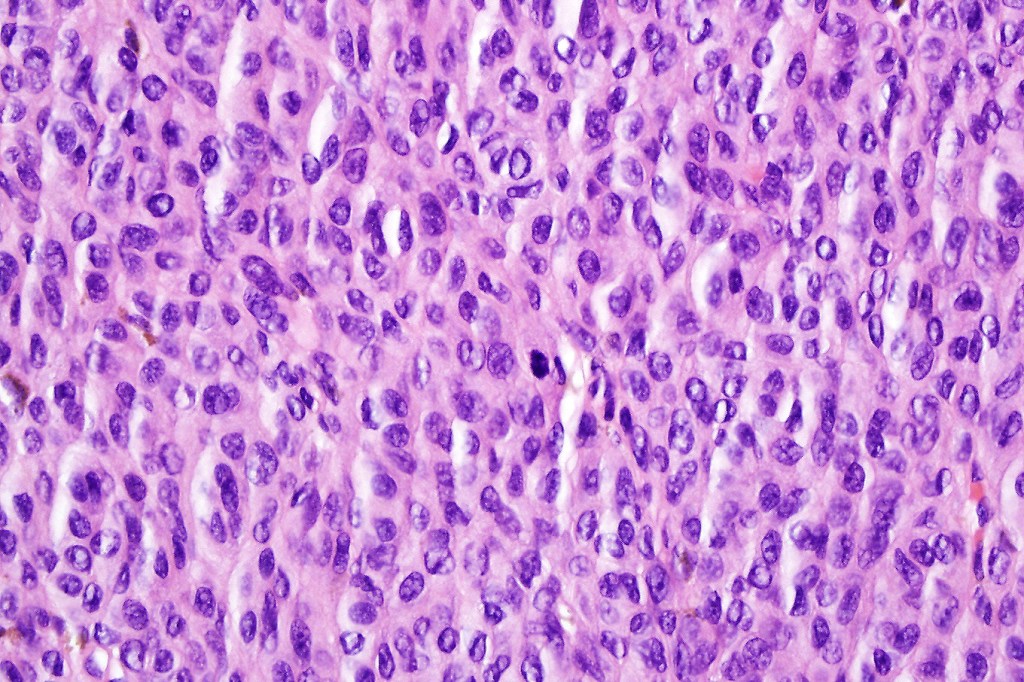

•It is hypercellular and most often composed of epithelioid cells showing little pleomorphism & only occasional mitoses

•Nuleoli are small

•Intracytoplasmic pseudo-inclusions

•The constituent cells are generally larger than the adjacent nevus cells

•Some examples show more marked pleomorphism with prominent nucleoli and increased mitotic activity but abnormal mitoses are not a feature. These are not associated with any sinister biological potential

•Absence of necrosis, hemorrhage or Pagetoid spread in the overlying epidermis

•Spindle cell, small blue cell, blue nevus-like features, Spitzoid & proliferative nodules with mesenchymal differentiation (myofibroblastic, chondroid & osteoid) can be seen